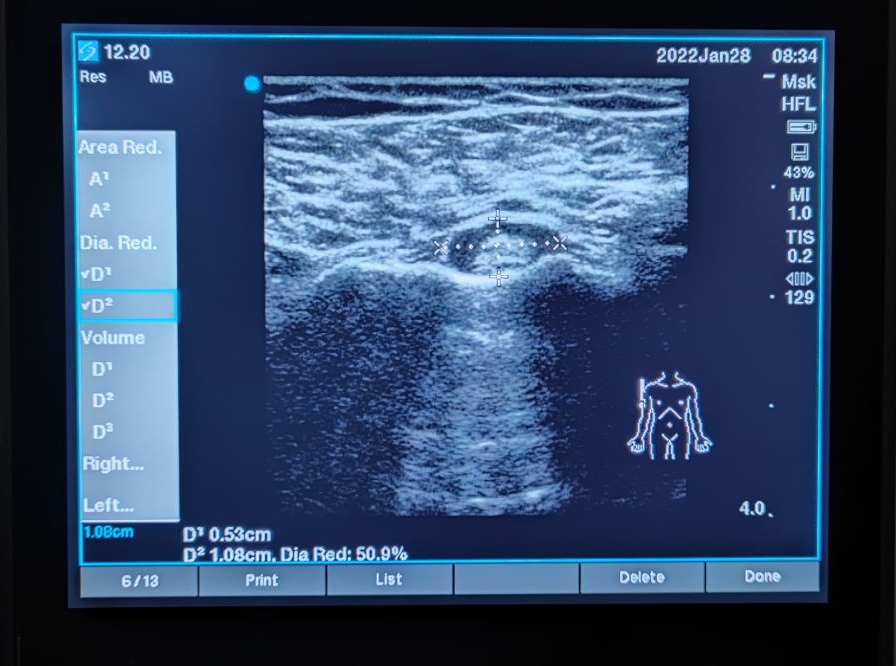

张大妈右肩肌骨超声检查声像图:

图一:冈上肌腱钙化

图二:肱二头肌长头肌腱鞘炎(短轴)

图三:肱二头肌长头肌腱鞘炎(长轴)

图一张大妈冈上肌腱的钙化灶,伴肌腱肿胀撕裂。图二、图三肱二头肌长头肌腱鞘积液。这两处是引起张大妈肩痛活动受限的主要问题,因反复的肩膀用力活动,造成肌腱慢性损伤,炎症渗出,逐渐产生积液、钙化,得不到良好的治疗和休息,疼痛会在某一刻爆发出来,困扰张大妈的生活。因此,张大妈的病情是慢性肩袖损伤合并肱二头肌长头肌腱鞘炎,治疗采用肌骨超声引导下肩关节穿刺注射技术。